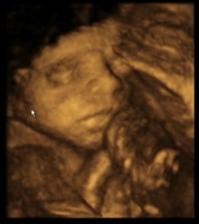

Dne 11.3.2009 nastal den D a já našla na těhotenském testu znovu // čárky. S manželem jsme si jisti, že tentokrát to dopadne dobře a my se konečně dočkáme našeho vytouženého zlatíčka.

Broučka jsme se opravdu dočkali. Dne 25.10.2009 v 19.24 hod. přišel předčasně na svět (35 tt). I když se narodil dříve, je to čiperka a má se čile k světu. Jmenuje se Matyášek a je to naše velké zlatíčko.